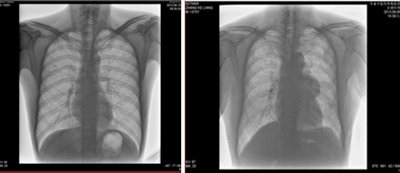

2. 數(shù)字化透視:

★通過透視快速定位,無需在控制室與檢查室往返。

★消除常規(guī)DR的盲拍,易于發(fā)現(xiàn)病灶,實現(xiàn)精細診斷。點片900萬像素,提高診斷效率。

★全身各部位透視(如胸透、腹透等)、透視下定位、透視下穿刺及透視下數(shù)字點片攝影。